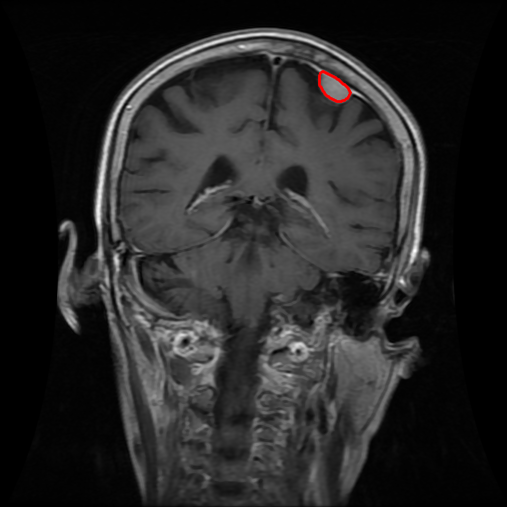

From the above discussions, we have discovered the significant potential of applying Retinex theory to image segmentation and explored its fundamental differences from traditional models. Traditional image segmentation models typically focus on the impact of intensity information on the segmentation results. Therefore, when faced with complex segmentation scenarios, the segmentation results are often affected by lighting, artifacts, and unclear boundaries in the image. As shown in Fig. 1, we present the results of the classical local model LIF [ZHANG20101199] for segmenting brain tumor images along with surrounding tissue edema. The irregular ring-like enhancement caused by the edematous tissue leads to irregular boundaries and low contrast in the images. Consequently, the LIF model can only identify the central necrotic and liquefied regions of the tumor, failing to detect the boundaries and becoming trapped in local minima. In this paper, we draw inspiration from the Retinex theory, which is widely applied in the field of image enhancement. According to Retinex theory, the reflectance component characterizes the intrinsic structural properties of the observed image and preserves texture information independent of illumination variations. By integrating this reflectance component into the level set framework, our model achieves robust segmentation of medical images even under severe intensity inhomogeneity. In addition, a linearized Structural-Prior is proposed to restore intensity consistency and capture local geometric features, thereby improving boundary localization in complex or blurred regions. Furthermore, a relaxed binary level set representation is employed to enhance robustness against noise and to enable accurate tracking of complex contours. Based on these innovations, we propose a novel variational reflectance-based level set model (RefLSM) that simultaneously corrects bias fields and performs segmentation. Experimental results demonstrate that RefLSM significantly outperforms conventional level set methods in both segmentation accuracy and robustness. We present the results of our model segmenting the two brain tumor images mentioned above in Fig. 2.

To address the challenge of segmenting images with severe intensity inhomogeneity, we propose a linearized structural prior that directly operates on the reflectance component . Reflectance-based structural information is more robust to illumination variations and bias field distortions, helping preserve weak edges and subtle anatomical boundaries. As shown in Fig. 2, our method can accurately delineate tumor boundaries and surrounding edema even under severe inhomogeneity, where traditional intensity-based models often fail. The proposed prior aligns smoothed reflectance gradients with data-driven directions, enhancing inter-region contrast, preserving weak edges, and stabilizing the evolution of . Formally, we define the linear structure operator as the gradient field of the smoothed reflectance:

Fig. 4 displays the visual comparison results for segmenting eight brain tumor MR images between the RefLSM and three representative models: the RESLS [8765635], ALF[MA2019201], and L1 model[LIU2019193]. These images exhibit severe intensity inhomogeneity and noise attributable to inconsistent bias field and imaging equipment. The initial level set function (LSF) initialization was consistent across all models, as shown in Fig. 4 (a), which illustrates the initial placement of the zero level contour. For visual clarity, we included the ground truth in Fig. 4 (f). The segmentation outcomes from the RESLS, ALF, and L1 methods are presented in Fig. 4 (b), (c), and (d), respectively.

It is evident from the first and last columns of Fig. 4 (b) that the ALF model tends to become trapped in local minima under severe intensity inhomogeneity. Furthermore, segmentation results presented in the columns 1-4 of Fig. 4 (b) and (c) reveal that both the ALF and L1 models mistakenly segment small isolated or irrelevant regions due to the effects of irregular intensity patterns. Additionally, when weak boundaries are present, as seen in the 1st and 3rd columns of Fig. 4, the RESLS, ALF, and L1 methods fail to accurately identify object boundaries. Consequently, the zero level contours of these models deviate significantly from the objects throughout the level set evolution, causing drastic misalignment after further iterations.

In stark contrast, our proposed method exhibits greater robustness against images exhibiting severe intensity inhomogeneity and weak boundaries. The proposed prior constraint term effectively corrects for intensity inhomogeneity, while the proposed binary level set adeptly reduces noise during the segmentation process.